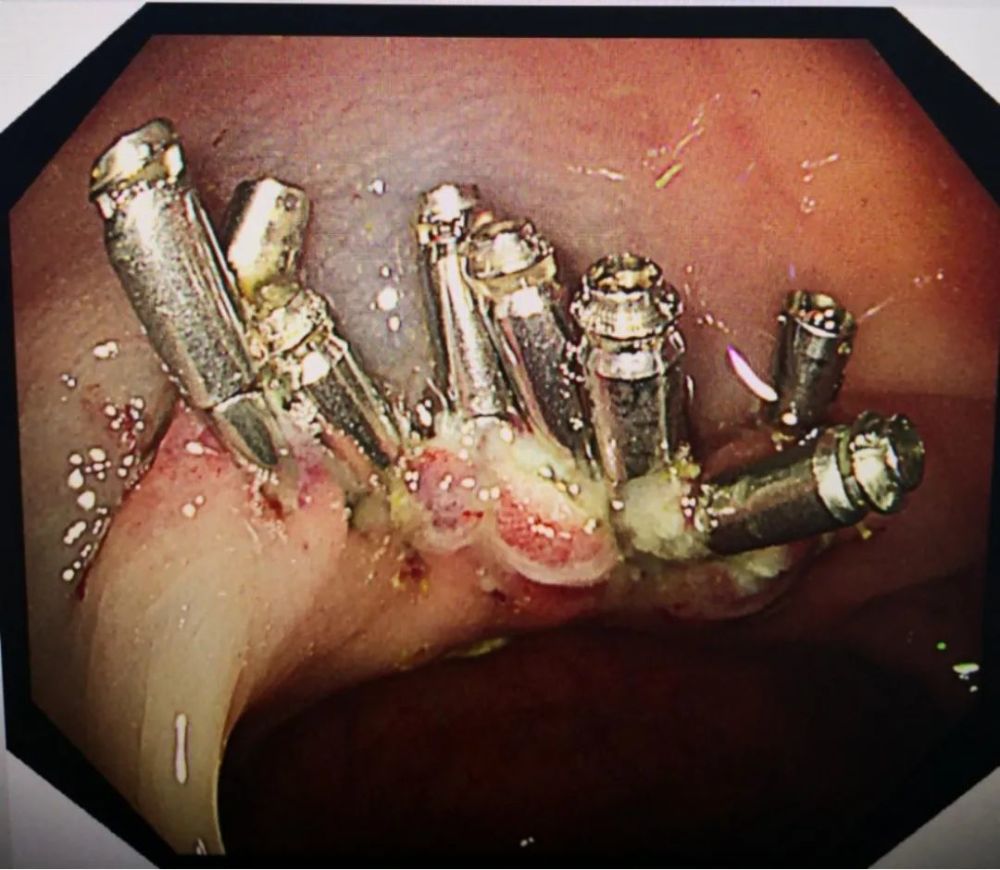

400余枚息肉藏肠内 中年女子腹痛10年 - 好大夫在线

图片尺寸2592x1936